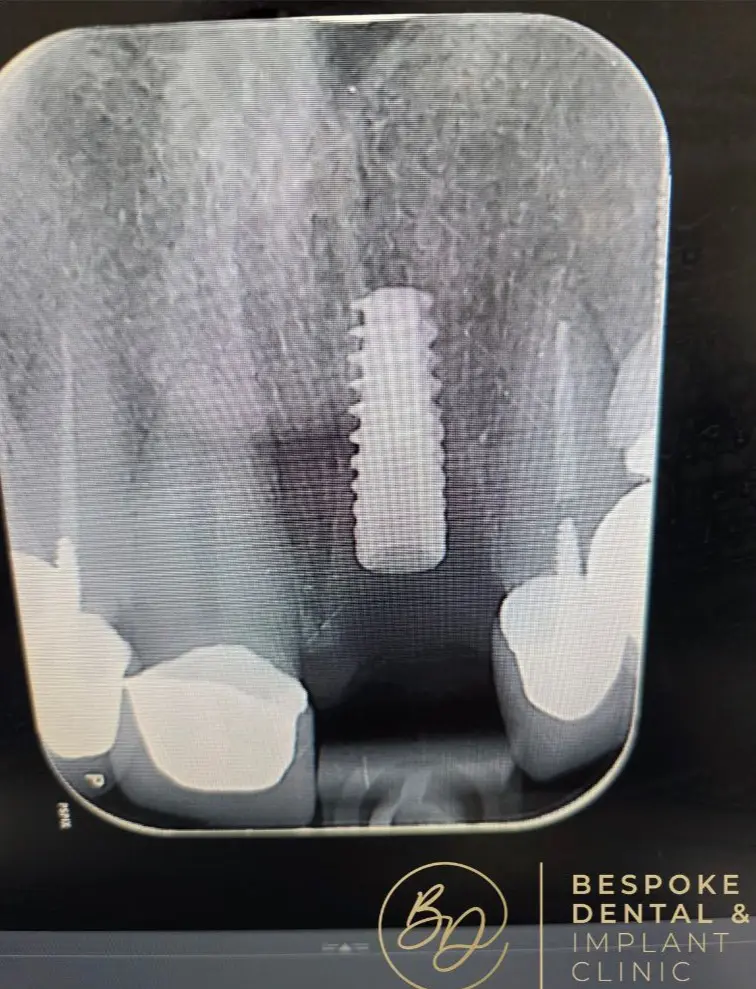

A dental implant is a screw-like metal post inserted into the jawbone. It acts as a natural tooth root and serves as a foundation for the replacement tooth, a custom-made dental crown that sits atop the implant.